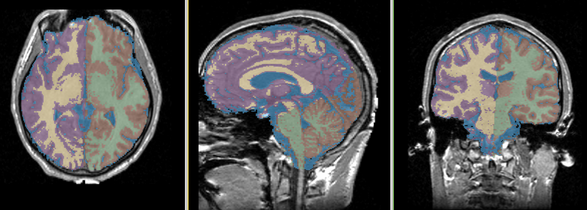

Single channel automatic segmentation of t1w-MRI brain scans into the major tissue classes (gray matter, white matter, csf). The task can only be applied to t1w brain scan showing parts of the skull and neck. The pipeline consist of the following steps:

Result